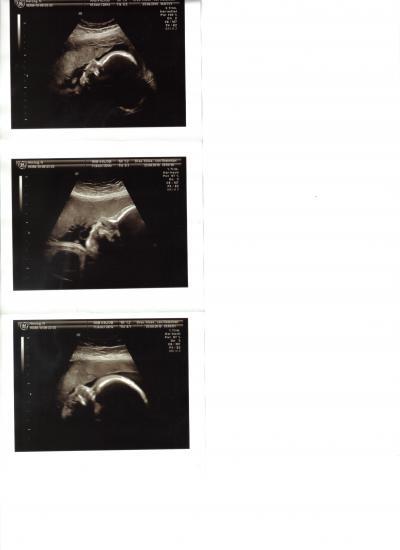

Die versprochenen Bilder von Gestern :-)

Unser Baby zum verlieben

Na das sind doch ein paar schöne Profilaufnahmen. LG - Dörte